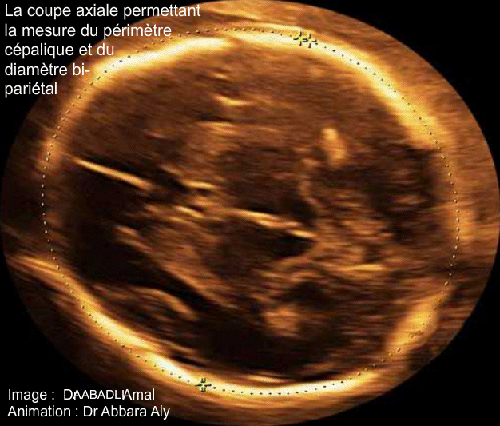

- Il s'agit d'une coupe transversale (axiale) de la tête fœtale ; sur cette coupe il faut réunir les paramètres suivants :

- Sur la coupe on doit mettre en évidence la ligne médiane du cerveau avec une symétrie exacte dans la position des éléments anatomiques qui se trouvent des deux côtés de cette ligne médiane.

- Dans la partie antérieure la ligne médiane on doit voir le cavum du septum lucidum (ou pellucidum), puis dans la partie centrale, on doit voir les deux thalami.

- Le cervelet ne doit pas être visible sur cette coupe.

- Le carrefour ventriculaire postérieur est individualisable sur l'hémisphère cérébral distal.

- La technique de mesure du diamètre bi-pariétal (BIP) est variable d'un auteur à l'autre ; certains auteurs mesurent la distance maximale séparant les deux os pariétaux en posant les curseurs au milieu de l'épaisseur de ces deux os ; d'autres auteurs mesurent cette même distance en posant le premier curseur sur la face extérieure de l'os pariétal proximal, et le deuxième curseur sur la face intérieure de l'os pariétal distal.

En effet, il faut connaître la technique de mesure utilisée par l'auteur pour établir sa courbe de référence, et quand on adopte une courbe comme une référence, il faut adopter en même temps la technique de mesure utilisée pour établir cette courbe.